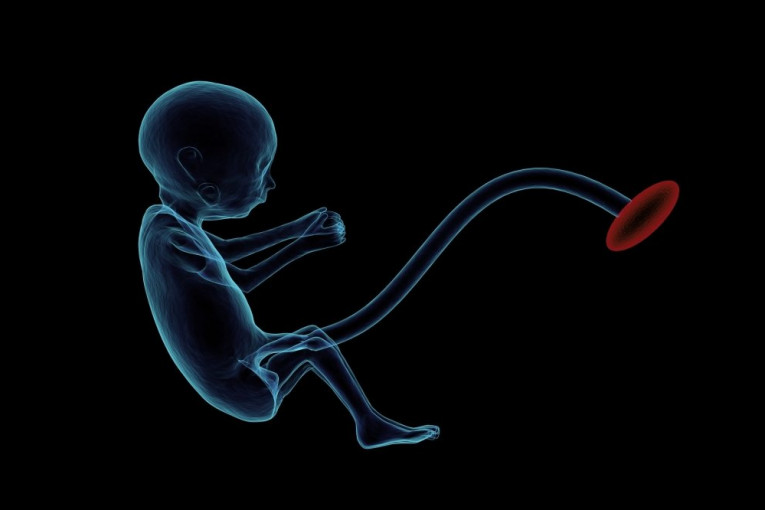

(FOTO) RAZLOG OPRAVDAN, PODVIG NEETIČKI: Španci razvili ljudsko-majmunski embrion u Kini

Španski naučnici stvorili su hibrid čoveka-majmuna u Kini, što je deo eksperimenta koji ima za cilj da se pronađe način kako da se razvijaju organi za transplantaciju.

Foto: pixabay.comEksperiment je izveo tim koji je predvodio naučnik Huan Karlos Izpisua tako što je ubrizgao ćelije u životinski embrion, prenosi španski El pais nazivajući taj embrion himerom, po biću iz grčke mitologije koje je delimično zmaj, delimično koza, a delimično lav, odnosno po imenu za organizme koji sadrže ćelije dve različite vrste.

Oni su genetski modifikovali embrione majmuna kako bi deaktivirali gene neophodne za formiranje organa, a zatim su u njih ubrizgali ljudske matične ćelije, koje mogu da stvore bilo koju vrstu tkiva u embrionu.

Kako se navodi, na taj način su dobili majmuna sa ljudskim ćelijama koji nije rođen, budući da su naučnici zaustavili proces.